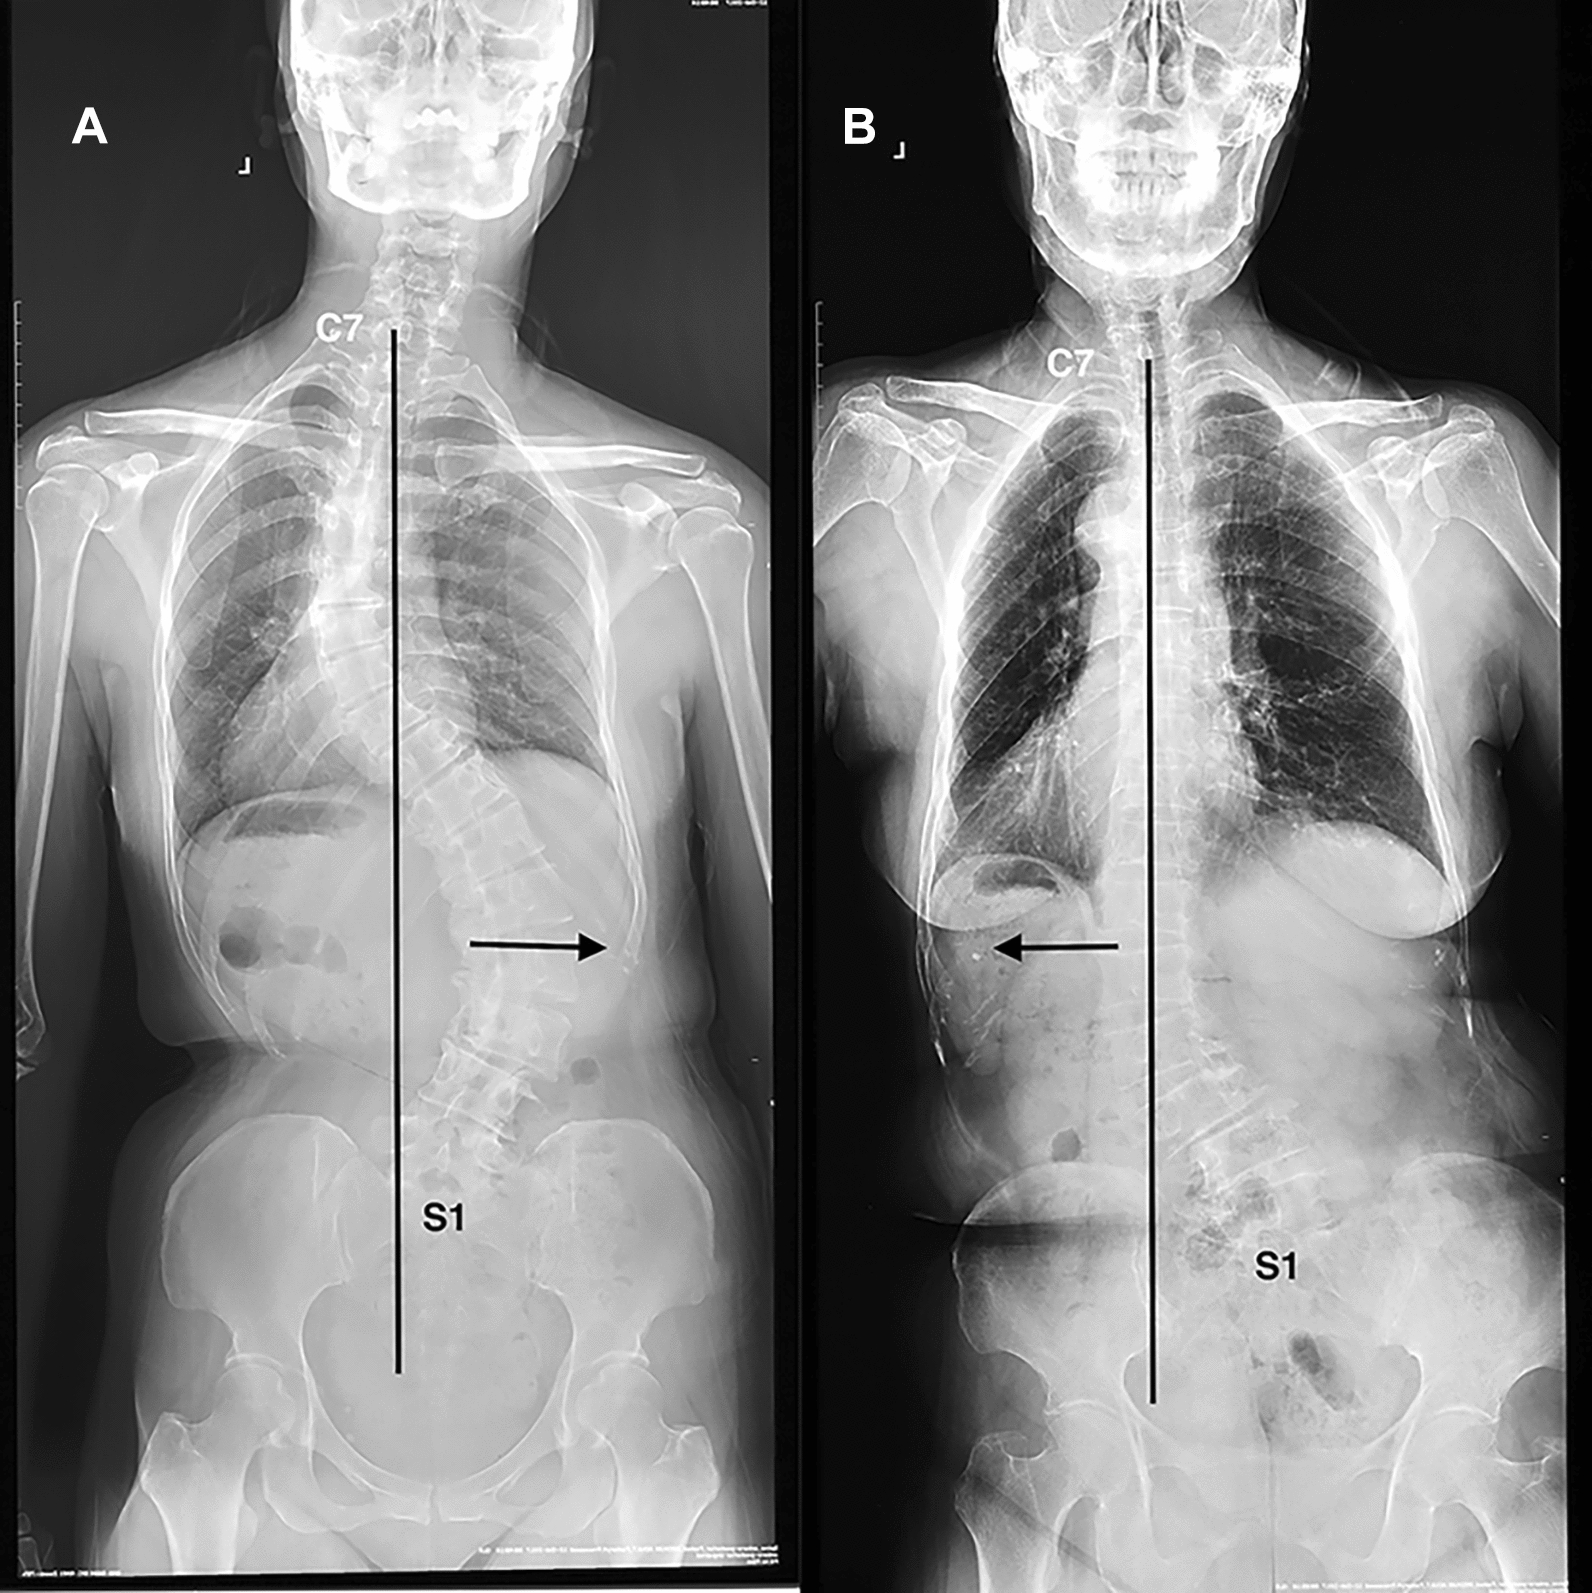

According to the orientation of major curve being relative to the C7 plumb line (C7PL) shifting on coronal images preoperatively, patients were subdivided into the consistency group (C7PL shifting towards the convex side) and the opposition group (C7PL shifting towards the concave side) (Fig. 2A, B) All of those radiographic parameters were measured by two independent spinal surgeons from the surgical team. Intra- and inter-rater reliabilities were excellent with the kappa values ranging from 0.889 to 0.938.